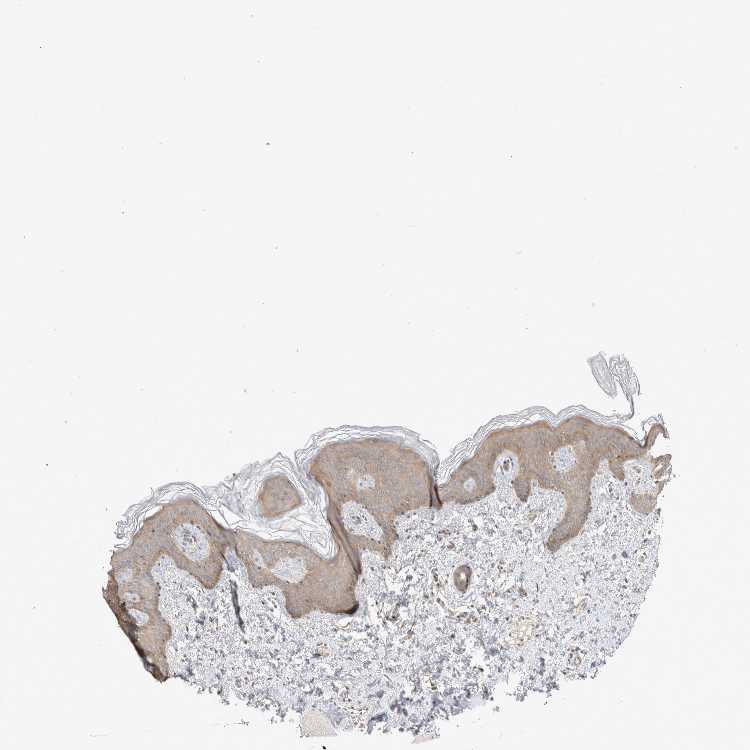

SKIN 2 - Antibody stainingi

Antibody staining in the annotated cell types in the current human tissue is reported as not detected, low, medium, or high, based on conventional immunohistochemistry profiling in selected tissues. This score is based on the combination of the staining intensity and fraction of stained cells.

Each image is clickable and will lead to virtual microscopy that enables deeper exploration of all samples and also displays staining intensity scores, fraction scores and subcellular localization as well as patient and tissue information for each sample.

Antibody HPA025958Antibody CAB020722

Epidermal cells MediumMedium